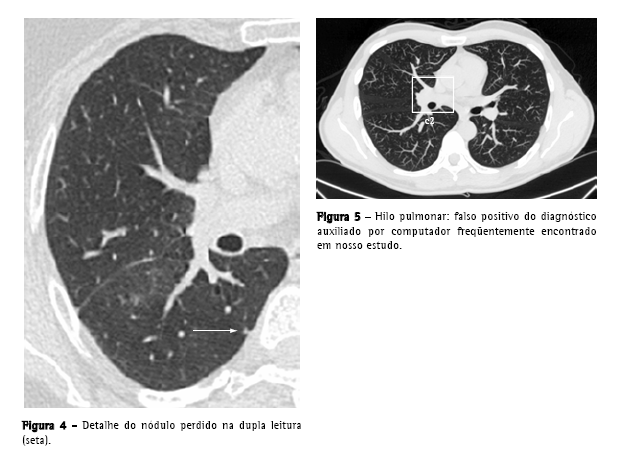

O número de falsos positivos por exame e por imagem (média de 322 imagens por exame) foi de 10,9 e 0,8 respectivamente; a razão falsos positivos/ verdadeiros positivos foi de 8,2:1. A maior parte dos falsos positivos foram vasos de pequeno e médio calibre (61,8%), estruturas do hilo (7,3%) e opacidades e consolidações (6,5%) (Figura 3).

Apenas um nódulo verdadeiro (<1% do total de nódulos verdadeiros), que foi destacado pelo DAC, não havia sido registrado no processo de dupla leitura das imagens. Este era subpleural, mal definido, media 4 mm, e localizava-se no lobo inferior direito (Figura 4).

A média de falsos positivos por exame (10,9), apesar de estar dentro da faixa encontrada em outros estudos, que varia entre 3 e 13 falsos positivos por TC de tórax,(21) não é desprezível, sendo um fator de desgaste e que consome tempo na revisão dos dados fornecidos pelo computador. Os falsos positivos encontrados foram, principalmente, estruturas vasculares, e estão de acordo com os referidos na literatura, exceto pelas estruturas hilares (Figura 5), que não são especificamente citadas com freqüência.(9,19,22)